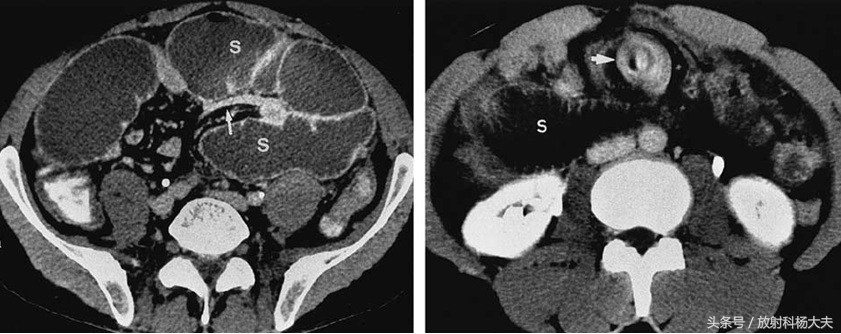

S代表扩张的肠管,左图白箭为鸟嘴征,右图为旋涡征

做完了后,我们在CT上看到了两个征象,鸟嘴征和旋涡征。所谓鸟嘴征就是扩张的肠管和萎陷的肠管的部位就像长长的鸟嘴;而旋涡征是肠系膜的血管在扭转后形成的,因此根据CT诊断为肠扭转。